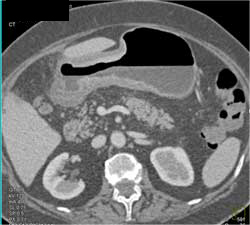

Linitis Plastica